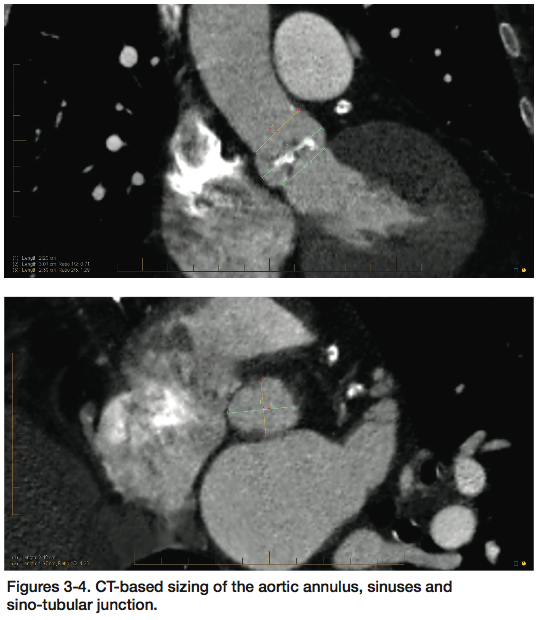

Given these considerations, she was felt to be an appropriate candidate for transfemoral TAVR and comprehensive pre-procedural testing was performed at Oklahoma Heart Institute, including transthoracic and transesophageal echocardiography, cardiac catheterization with coronary and bypass graft angiography, as well as computed tomographic (CT) evaluation of the aortic valve/annulus, aorta and iliofemoral vessels (Figures 2-5). These studies were performed, interpreted and reviewed by the multidisciplinary Heart Team at Oklahoma Heart Institute, and the patient was felt to be an appropriate candidate for transfemoral TAVR utilizing a 23 mm Edwards Sapien transcatheter heart valve.

Yes. This procedure is complex enough that it necessitates all that testing be done before we can even know if a patient is a candidate. Patients must have coronary angiography and a cardiac cath to evaluate their coronary anatomy, aorta and iliac vessels. Similarly, a CT scan is done to assess their native aortic valve and annulus size, and assess for suitability of transfemoral access. We try to space all those procedures out over the course of weeks to mitigate the risk of contrast-induced nephropathy. Clearly each of these procedures, cath, CT, and TAVR, have radiation associated with them. However the radiation doses are small with each of these tests, and these patients are relatively elderly, so things like the risk of cancer due to procedural radiation are not a big concern. The deterministic effects of radiation are always a concern, but we strive very hard to limit radiation doses and thus far we have not had a problem.